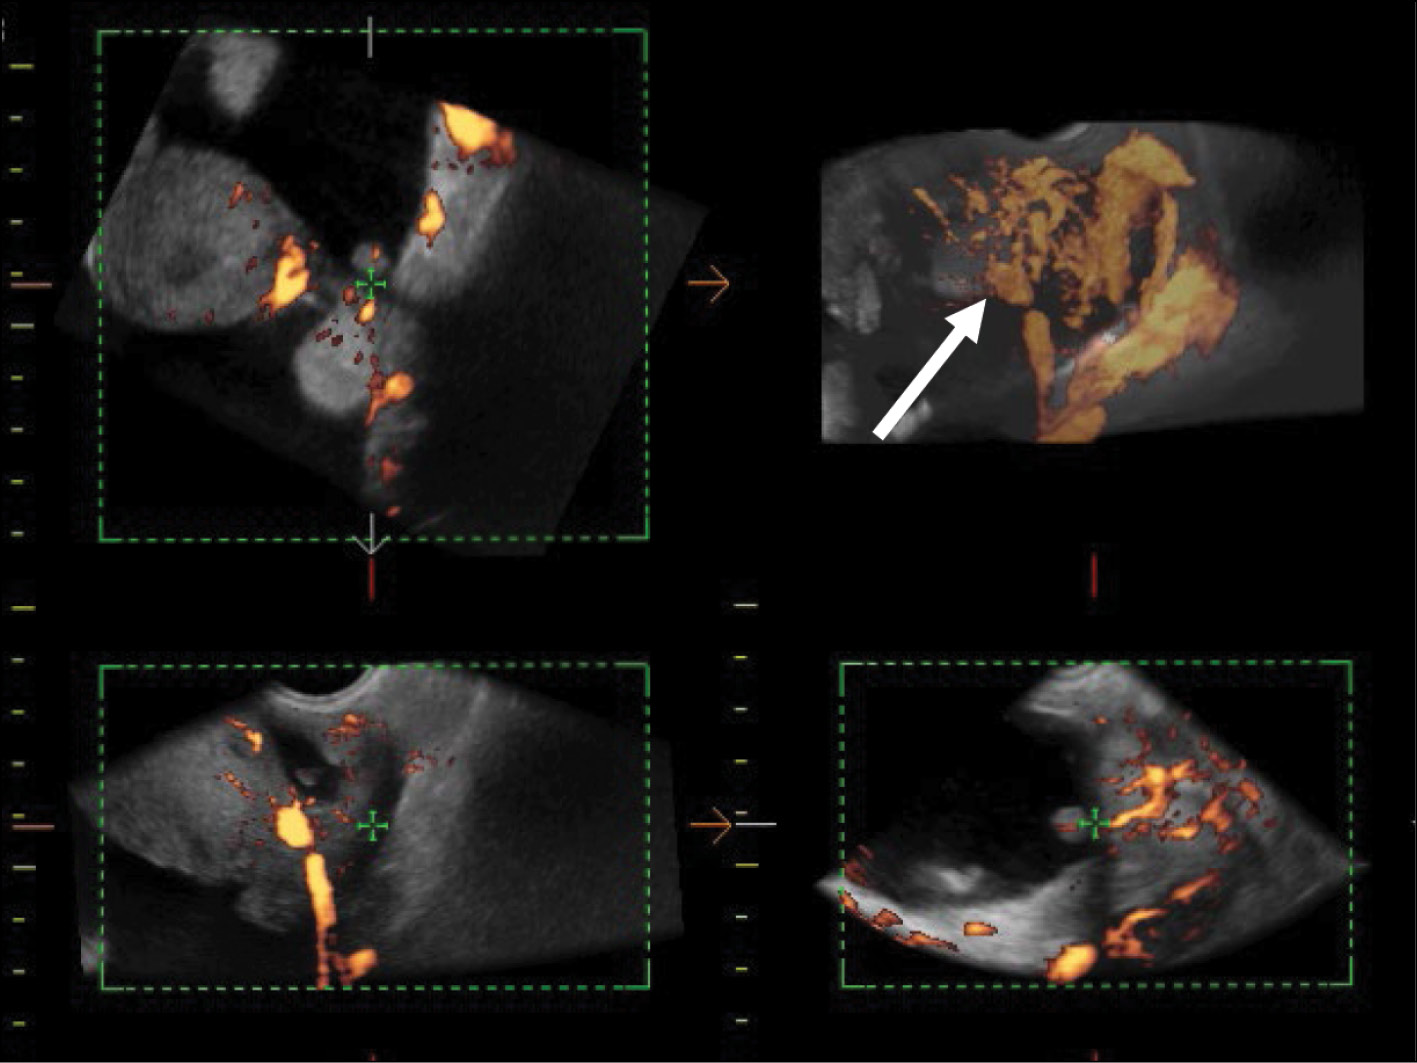

The intensity of the blood flow in the tumor lesion in the retrouterine pouch is remarkable, as well as its smoothness in the thickened (up to 5–7 mm) peritoneum of the small pelvis (Fig. 3).

Fig. 3. 3D angiography of the malignant struma lesion along the peritoneum in the retrouterine space (arrow).

US demonstrated that the recurrent lesion of malignant struma ovarii along the pelvic peritoneum, identified in the presence of ascites, had an iso-hypoechoic structure with fuzzy contours and small size (4–12 mm). The peritoneum of the small pelvis outside the lesion was <4 mm thick; however, 3D angiography and US-CT revealed that even small blastomatous lesions were well vascularized. Blood flow was also present in the 4–5 mm thick structure of the pelvic peritoneum (Figs. 5–7).

Fig. 6. US-CT of the recurrent lesions of the malignant struma ovarii.

Fig. 7. 3D angiography of the recurrent lesions of the malignant struma ovarii in the pelvic peritoneum in the presence of ascites.